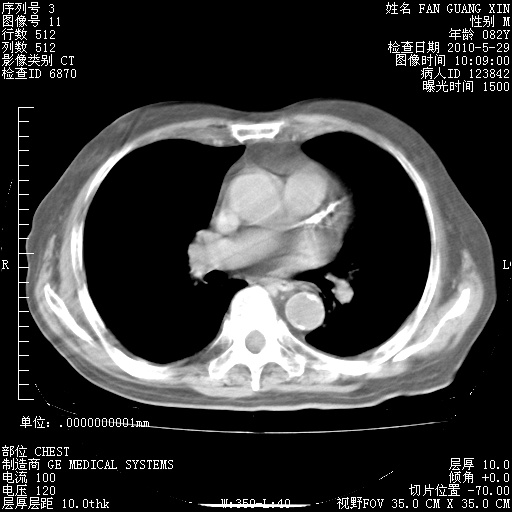

再治疗10天后的肺部CT

肺部体征:呼吸25次/分,心率100次/分,呼吸音增粗。无干湿罗音。

血常规:15.36×10 [sup]9[/sup]/L  N0.92  L0.036  M0.045 ESR 27mm/h。

血生化:白蛋白33.30g/L  球蛋白23.67g/L  CRP 32.82mg/L 肝肾功能正常。电解质正常。

从白细胞总数和中性比例看好像合并感染。肺部纹理好像比上次多,支气管炎?其他感染?

阅读此次胸部CT,肺间质渗出性改变较入院时有吸收。目前从体温、白细胞、中性分叶明显增高,肯定存在细菌感染(发生医院感染哦,若无消化道及泌尿系统等感染的依据,肺部感染可能大)。若你院头孢哌酮舒巴坦钠耐药率较高,同意你的方案,若48小时体温仍高,可考虑使用碳青霉稀类抗菌药物,同时可予超声雾化、注意滴数时加大液体量。白蛋白33.30g/L较低哦,需加强营养等支持治疗。